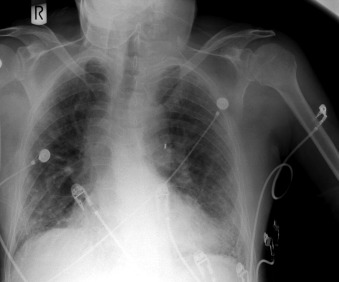

Pulsatile Devices: Intra-aortic Counterpulsation Balloon ( Figs. 24-1 to 24-7 )

The tip of an intra-aortic balloon (which is highly visible because of its metallic marker) should be at least 4 cm below the “knuckle” of the aorta (i.e., below the left subclavian artery). The balloon appears as a cylindrical lucency if the radiographic exposure happened to be while it was inflated in diastole. Widening or haziness of the aorta suggests aortic dissection as a complication of the catheter. Incorrect insertion into the inferior vena cava is suggested by the shadow of the catheter lying to the right of the patient’s vertebral column.